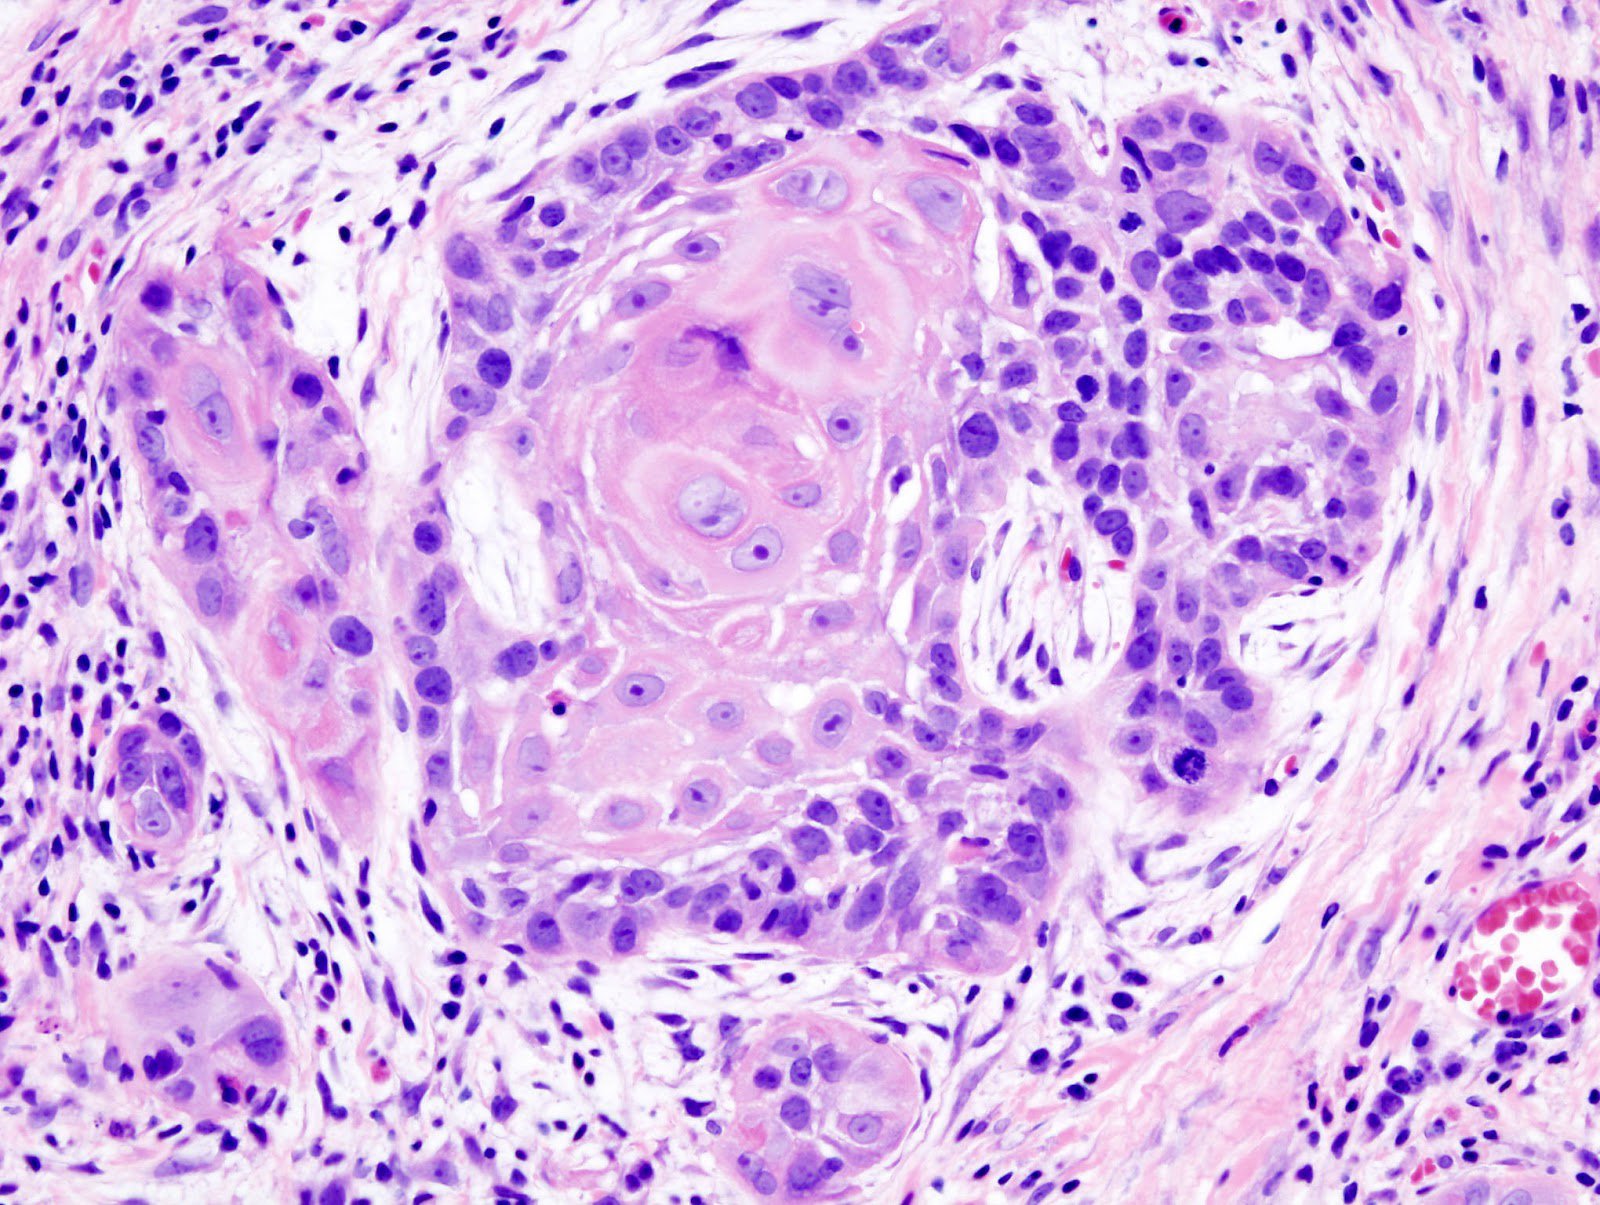

Hóa mô miễn dịch là một kỹ thuật được sử dụng để phân biệt giữa u ác tính và u lành tính. Đây là một phương pháp chẩn đoán quan trọng trong lĩnh vực y học, giúp xác định tính chất của u và đưa ra kế hoạch điều trị phù hợp.

Hóa mô miễn dịch là một phương pháp chẩn đoán có độ chính xác cao trong việc phân biệt giữa u ác tính và u lành tính. Tuy nhiên, như với bất kỳ phương pháp chẩn đoán nào khác, độ chính xác của kết quả phụ thuộc vào nhiều yếu tố, bao gồm chất lượng mẫu u và kỹ năng của người thực hiện.